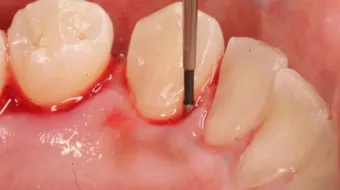

هو عبارةٌ عن طبقةٍ لزجةٍ بيضاء من اللعاب والبكتيريا، وبقايا الطعام، وتتكوّن هذه الطبقة على أسطح الأسنان وتنجم عن إهمال نظافة الأسنان والفم، حيث تتراكم عليها وتتصلب بحيث تصبح على شكل حصى متماسكة، والتي تتسبب في العديد من الأضرار للثة والأسنان، حيث تُسبب التهابات وآلاماً، ونزيفاً، وإحمراراً في اللثة، وإنّ إهمالها لفترةٍ طويلةٍ قد يتسبب في حدوث ارتخاءٍ للأسنان مؤدياً إلى اقتلاعها، وتجنباً لهذه الأضرار لا بدّ من التخلص منه بأسرع وقتٍ ممكن، وفي هذا المقال سنذكر كيفية التخلص من جير الأسنان.[1]